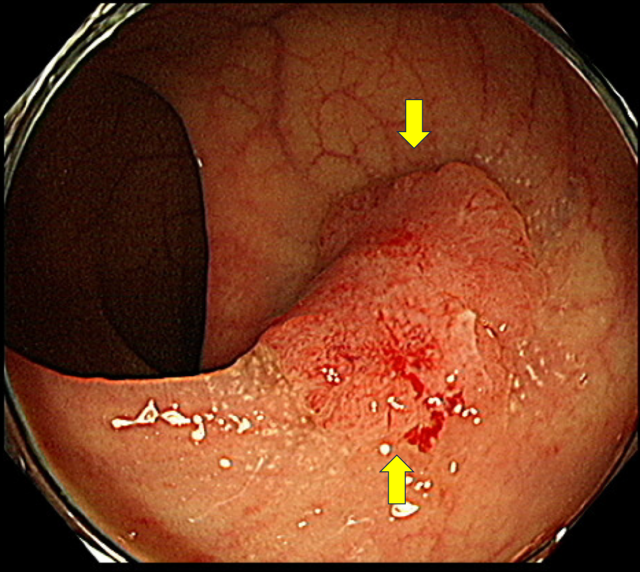

대장내시경 검사 결과 조기 대장암(노란색 화살표) 소견이 관찰된다. 사진 제공=서울아산병원

조기 대장암은 대부분 별다른 자각 증상이 없다. 대장암 중 일부는 표면에서 간헐적으로 소량의 출혈이 발생하는 소견을 보인다.

대장암이 의심될 때 가장 먼저 대변 속에 혈액이 있는지 확인하는 대변잠혈검사를 시행하는 이유다. 대변잠혈검사에서 혈액이 검출되면 정확한 진단을 위해 대장내시경검사를 시행하게 된다.